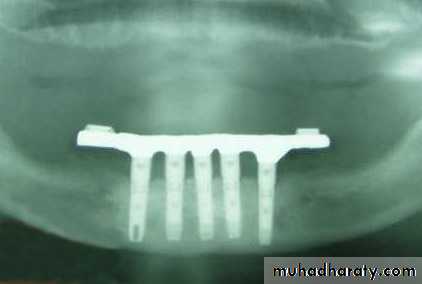

Transosteal / Transosseous Implant

Also called as Staple Bone Implant, Transmandibular ImplantPenetrates both cortical plate and passes through the entire thickness of the alveolar bone

Use restricted to anterior area of mandible

It is not used much any more because they necessitate an extraoral surgical approach.